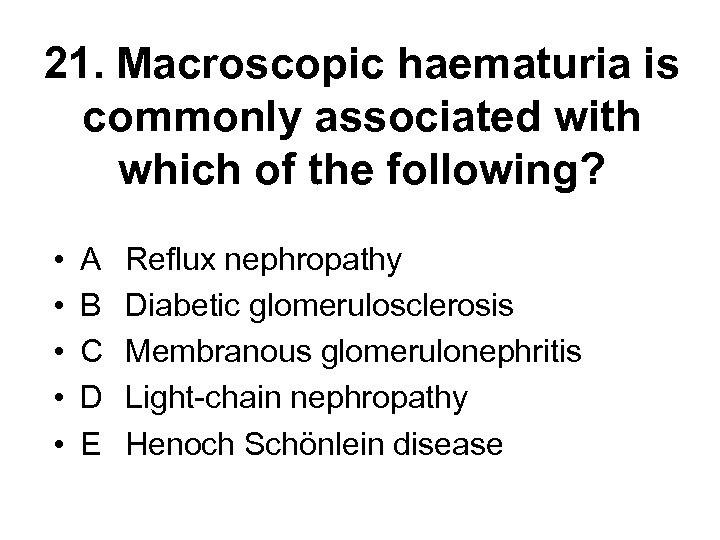

21. Macroscopic haematuria is commonly associated with which of the following? • • • A B C D E Reflux nephropathy Diabetic glomerulosclerosis Membranous glomerulonephritis Light-chain nephropathy Henoch Schönlein disease

21. Macroscopic haematuria is commonly associated with which of the following? • • • A B C D E Reflux nephropathy Diabetic glomerulosclerosis Membranous glomerulonephritis Light-chain nephropathy Henoch Schönlein disease

21. Macroscopic haematuria is commonly associated with which of the following? • • • A B C D E Reflux nephropathy Diabetic glomerulosclerosis Membranous glomerulonephritis Light-chain nephropathy Henoch Schönlein disease

21. Macroscopic haematuria is commonly associated with which of the following? • • • A B C D E Reflux nephropathy Diabetic glomerulosclerosis Membranous glomerulonephritis Light-chain nephropathy Henoch Schönlein disease